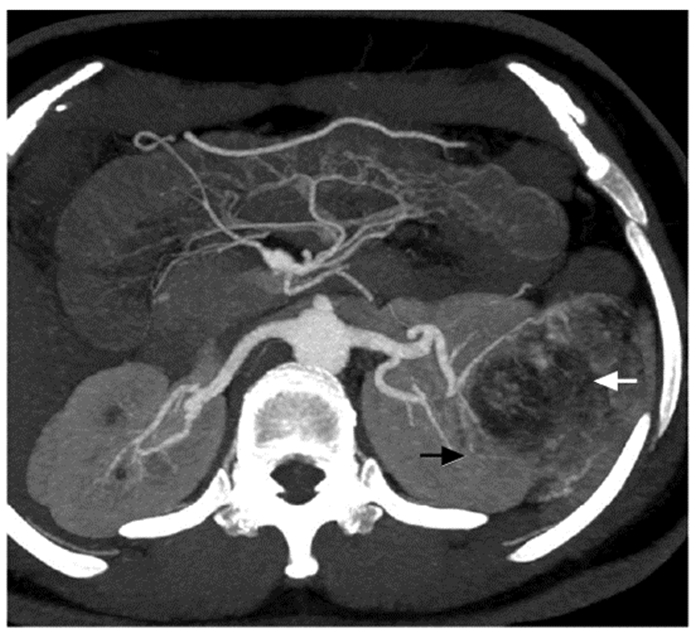

结果   14例AML患者中有1例相对孤立肾合并AML、7例多发AML、8例巨大AML(肿瘤最大直径>7 cm)、6例紧邻肾集合系统或肾门的AML以及2例合并出血破裂史AML, 病情复杂, 手术难度大。采取经腹腔镜或开放肾部分切除或肿瘤剜除术后, 顺利切除肿瘤, 病理检查提示肾AML, 术后定期门诊随访, 行CT扫描均无复发。全部患者术后肾功能保持良好, 术前和术后1个月血肌酐水平分别为(84.1±26.8)μg/ml和(97.5±37.0)μg/ml, 两组数据差异无统计学意义(t=-3.193, P>0.05)。

Results  Among 14 patients with renal AML, 1 had a relative solitary kidney with AML, 7 had multiple AML, 8 had huge AML (the maximum diameter of the tumor >7 cm), 6 had AML adjacent to the renal collection system or the renal portal, and 2 had AML combined with bleeding and rupture history; all cases were complicated and difficult to treat. All operations were successfully performed by laparoscopic or open partial nephrectomy or enucleation of the tumor, and pathological examination indicated renal AML. All patients were regularly followed up and no recurrence was found by CT scanning. The renal function of all patients was well preserved; the concentration of serum creatinine before and 1 month after the operation were (84.1±26.8)μg/ml and (97.5±37.0)μg/ml respectively, without statistically insignificant difference (t=-3.193, P>0.05).